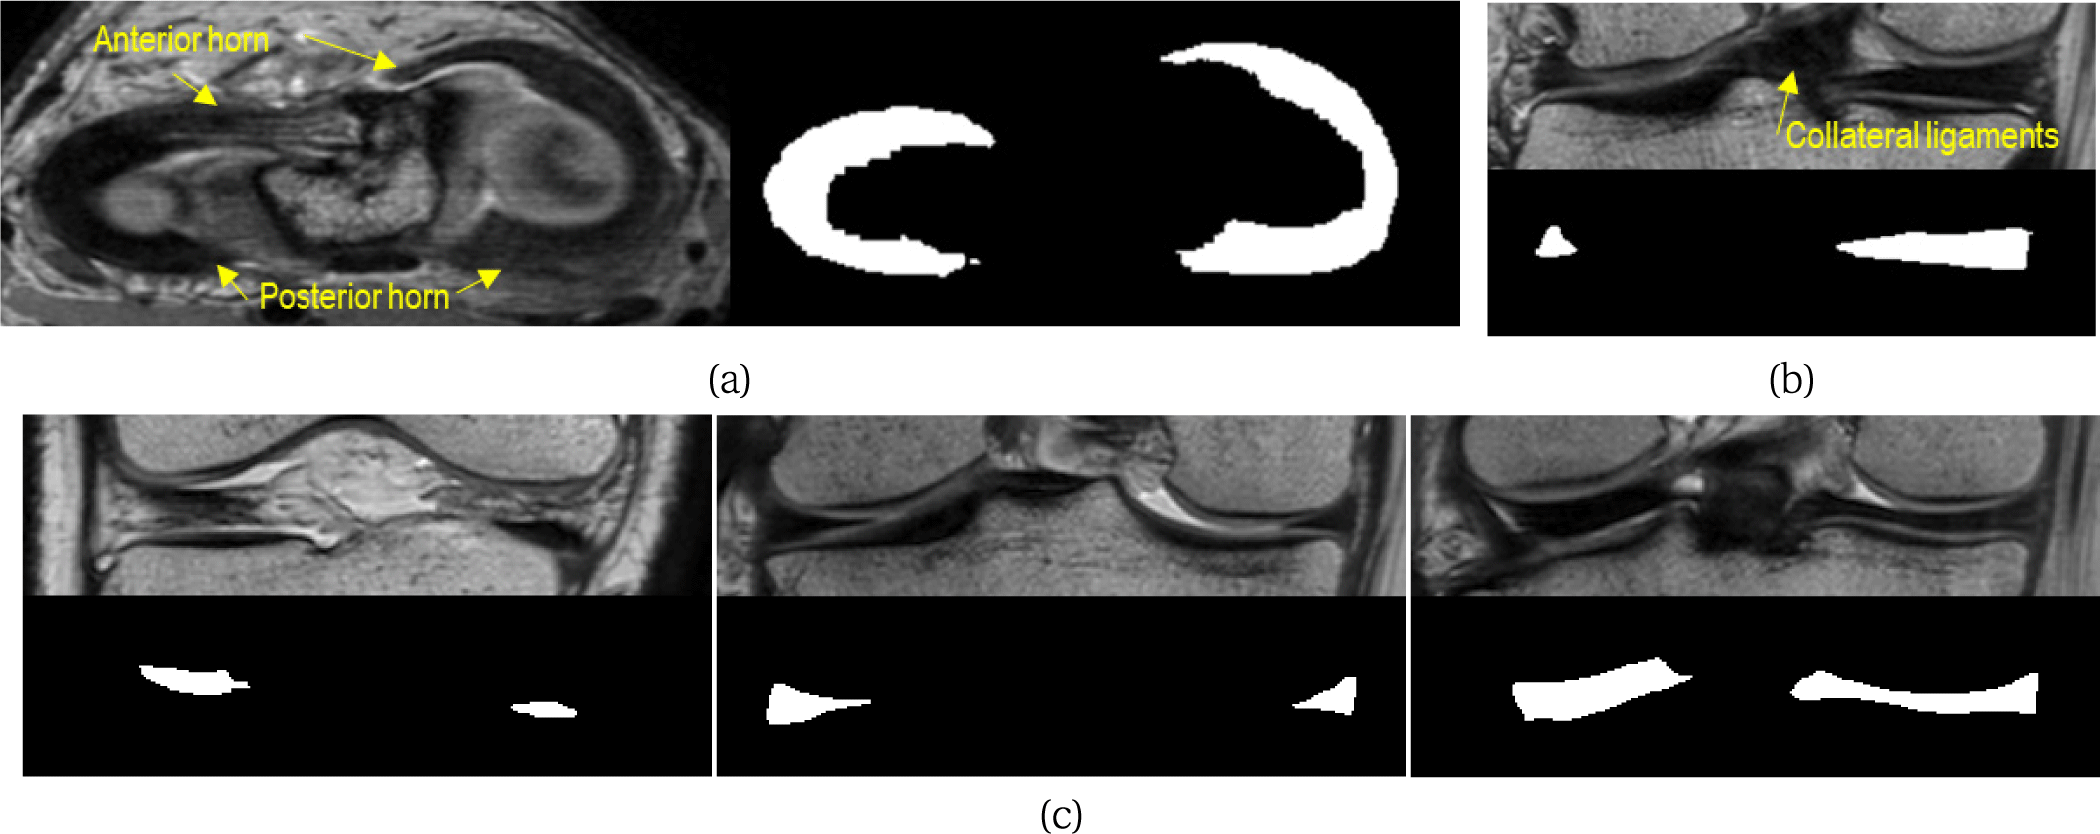

Joint Image-Mask Conditional Diffusion for Robust Meniscus Segmentation in Knee MR Images

J Korea Comput Graph Soc 2026;32(1):13-20.

https://doi.org/10.15701/kcgs.2026.32.1.13